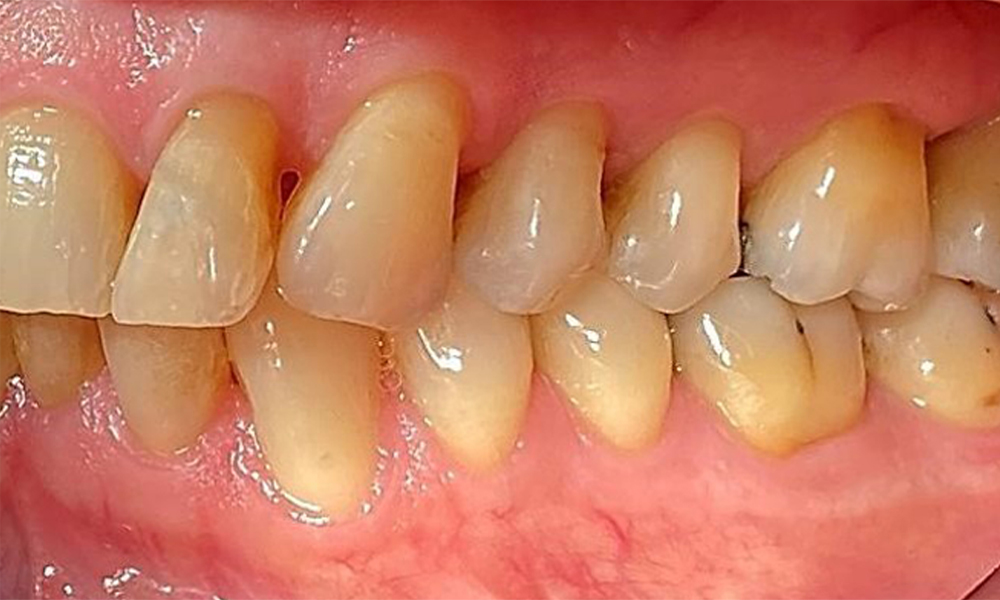

Пациентът има пълно съзъбие с 28 зъба, което включва амалгамни и композитни пломби в областта на моларите и премоларите. На зъб 14 има видима клинична маргинална празнина. Зъб 27 има адекватна златна инкрустация. Налице са и генерализирани атриции и абразии. (фиг. 2, фиг. 3, фиг. 4, фиг. 5, фиг. 6)

Пациентът е с пародонтит II стадий, степен В (5). Клиничните дълбочини на сондиране от 1 до 3 mm са във физиологичния диапазон. Локализирани дълбочини на сондиране от 5 mm са наблюдавани медиопалатинално на 17 и 27. Налице са генерализирани рецесии от 1 до 3 mm с частична загуба на интердентални папили (фиг. 2, фиг. 3, фиг. 4)